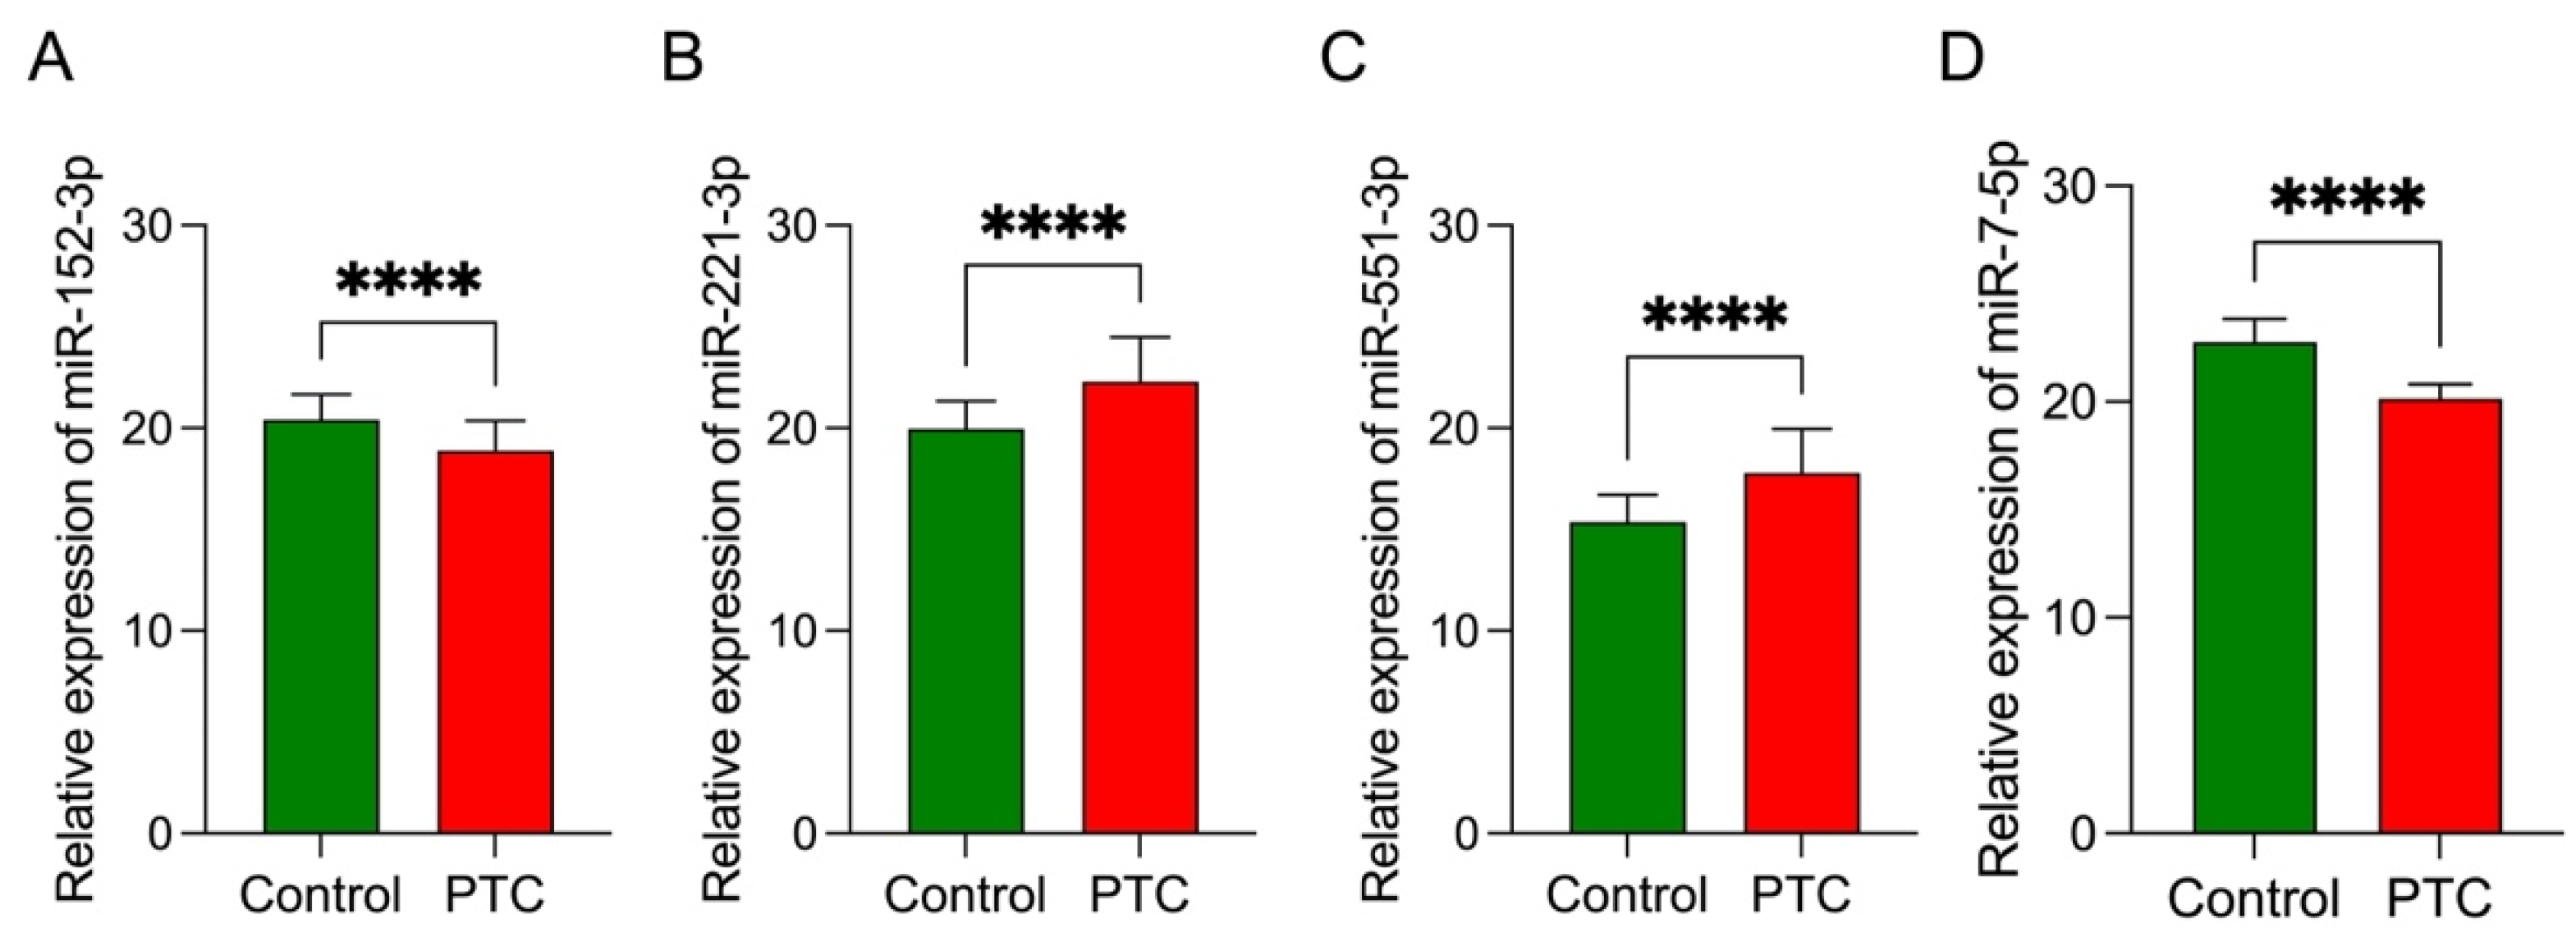

3.7. Data Validation

| Model | TP Rate | FP Rate | Precision | AUC | Intercept | Coefficient |

|---|---|---|---|---|---|---|

| x1 = miR-152-3p | 0.769 | 0.227 | 0.774 | 0.841 | −1.8033 | a1 = −1.2104 |

| x2 = miR-221-3p | a2 = 0.8173 | |||||

| x3 = miR-551b-3p | a3 = 0.5172 | |||||

| x4 = miR-7-5p | a4 = −0.0178 |